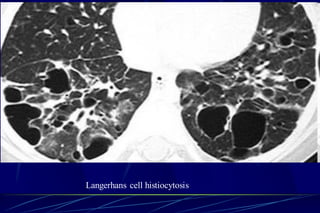

Langerhans Cell Histiocytosis

HRCT Findings

Small peribronchiolar nodules (1-5mm)

Thin-walled cysts (< 1cm),

Bizarre and confluent

Ground glass opacities

Late signs: irreversible / parenchymal fibrosis

Honey comb lung, septal thickening, bronchiectasis

Langerhans Cell Histiozytosis

Key Features

Upper lobe predominance

Combination of cysts and noduli

Characteristic stages

Increased Lung volume

Sparing of costophrenic angle